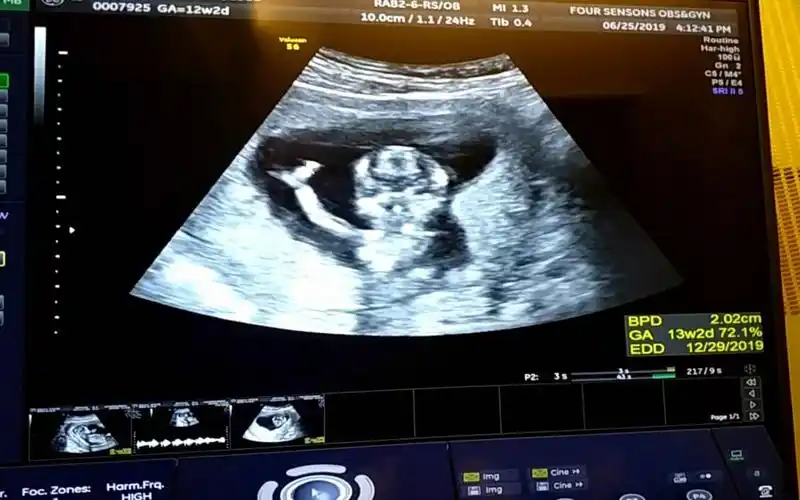

怀孕13周四维彩超产检实录,幸运的拍到了宝宝朝我们挥手致意!